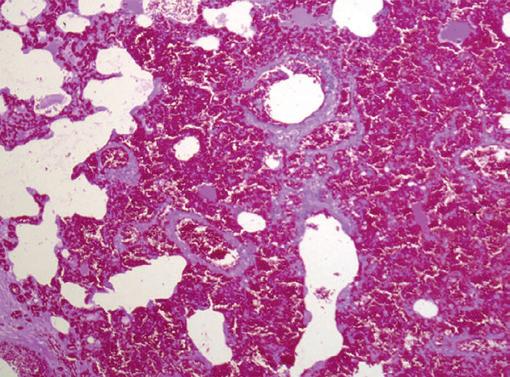

Returning to training, Oyster placed in six of her subsequent eight starts, winning the last two. She subsequently died suddenly during early training as a four-year-old. At post-mortem, diagnoses of pulmonary hemorrhage and exercise-induced pulmonary hemorrhage were established—a very frustrating and unfortunate outcome.

ABOVE: Microscope section of lung tissue from a horse that died in a severe episode of bleeding. Many alveoli (air sacs) and small airways are filled with red blood cells. Image courtesy Dr. J. Caswell, University of Guelph.